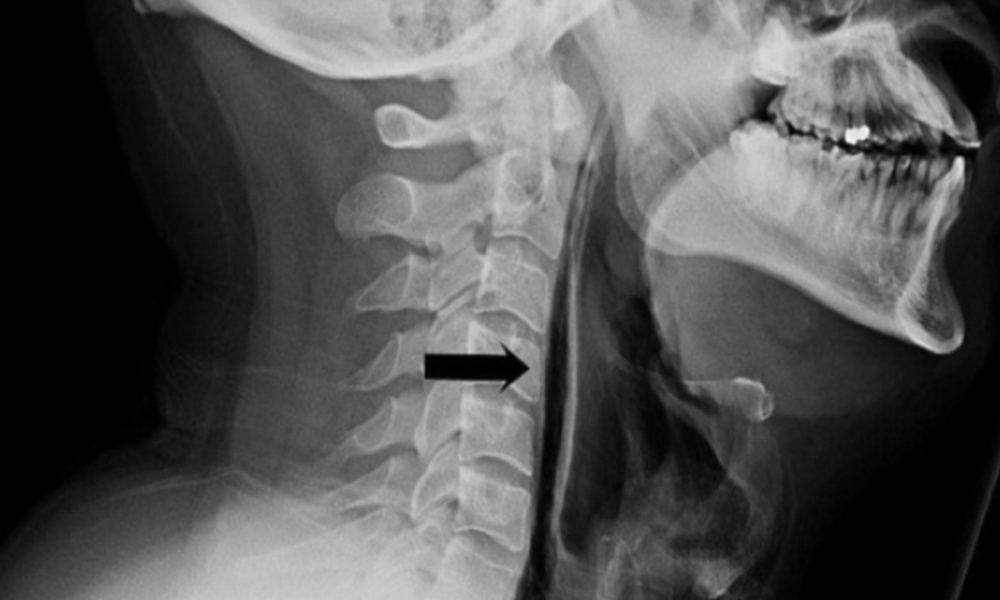

Житель Карелии порвал себе глотку во время чихания.

34-летний мужик пытался сдержать чих и зажал нос. Когда гений всё же чихнул, то ощутил толчки в шее — через время она опухла. У бедолаги случился спонтанный разрыв пищевода.

Врачи рекомендуют не закрывать нос при чихе, так как это может привести к разрыву аневризмы головного мозга.